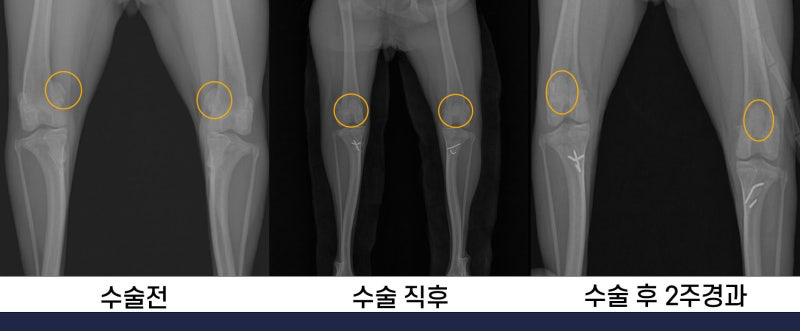

수술 직 후의 사진입니다. 미끄러져있던 슬개골이 정상위치(무릎중앙)으로 돌아온 것이 확인됩니다.

수술 전, 수술 직후, 수술 후 2주 경과한 환자의 x-ray 사진입니다.

이 환자는 수술 이후, 실밥까지 다 뽑고나서 확인하였을 때 다리를 더이상 들지 않는 모습이 확인되었습니다.